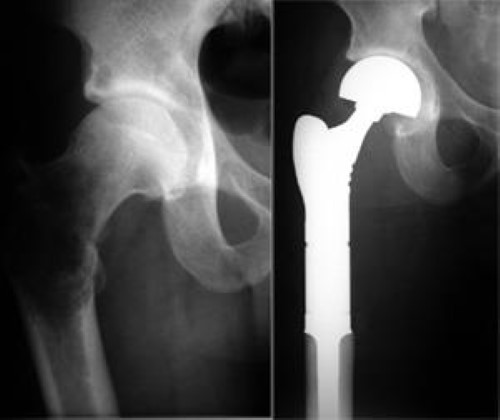

전이성 골종양의 경우 영상과 같이 치료가 무척 어렵습니다. 지푸라기라도 잡는 마음으로 방사선치료와 항암화학요법을 할 수 있습니다. 5년 생존율이 높아 보이는 환자군에서 장관골과 골반골의 임박 골절, 병적 골절 에는 예방적 고정술을 해볼 수 있습니다. (RT에도 효과가 없고, 2.5cm 정도로 큰 사이즈와 cortex가 50%이상 파괴되어 부러지기 직전일때, 소전자의 견열골절이 있을때 = Mirel 8점이상)